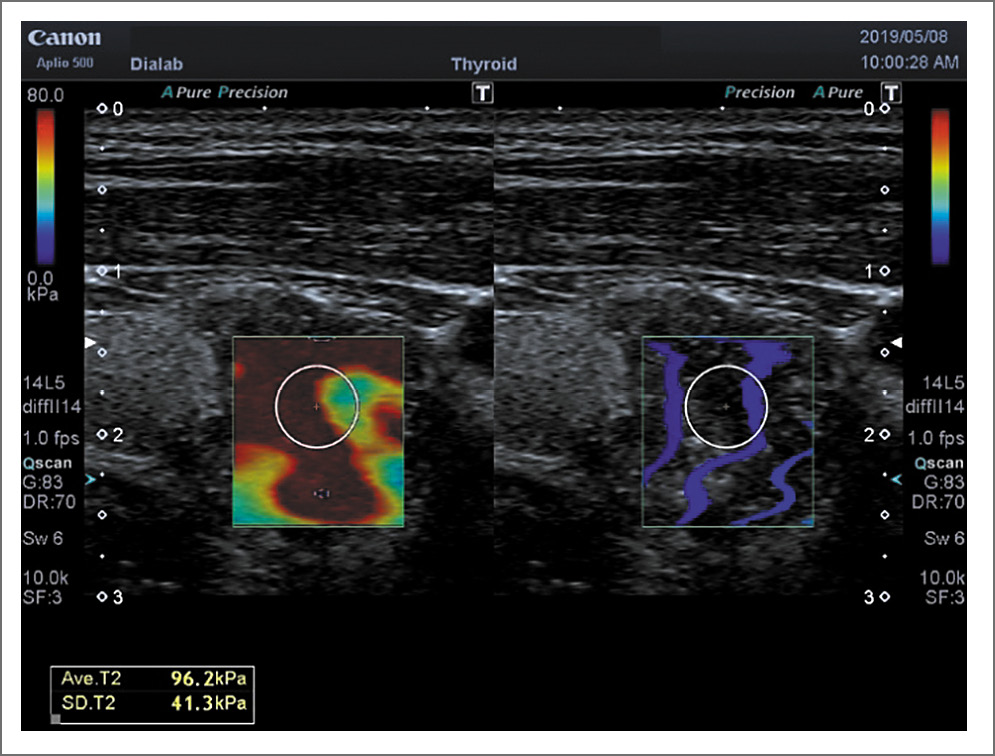

В литературе имеются единичные работы, посвященные этой проблеме. Так, F. Magri и соавт. (2012 г.) сравнили индекс эластичности нормальной ткани ЩЖ и при АИТ (24,0±10,5 кПа против 20,8±10,4 кПа; p=0,206). Авторы не получили также достоверных различий при соноэластографии доброкачественных УО при неизмененной паренхиме и на фоне АИТ [27]. По данным наших исследований модуль Юнга при АИТ составляет 32,05±2,14 кПа, что с высокой степенью достоверности (p<0,000) отличается от неизмененной паренхимы (15,9±0,87 кПа). При ПРЩЖ модуль Юнга достоверно выше (p<0,02), когда последний выявляется на фоне АИТ, чем без наличия фоновой патологии (72,03±1,09 и 67,0±1,9 соответственно); см. табл. 2, рис. 5, 6. Данные результатов наших исследований относительно доброкачественных УО (аденома, коллоидный зоб) показали те же закономерности и приведены в других публикациях.

Рис. 6. ПР на фоне АИТ. Shear Wave – 96,2 кПа